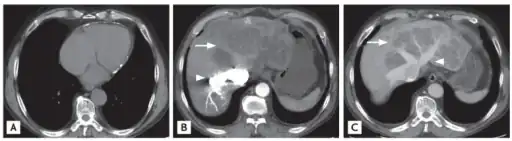

a) Sparse pericardial calcification with eccentric wall thickening b,c) liver CT shows variable regions of low attenuation, often called the “nutmeg liver” arrows -

CT appearance of liver in congestive hepatopathy, sometimes referred to as a nutmeg liver. Due to congestion, contrast does not flow through the liver in a normal manner. Axial and coronal images in the portal venous phase.